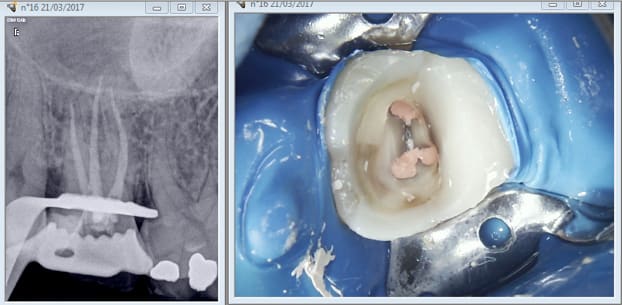

Je suis dans l'indication de l'onlay si j'estime que la pulpe n'est pas nase, je

suis dans l'indication de l'endo si j'estime le contraire. Enfin pour le SC33 ou

l'ic la décision se prend après préparation périphérique. Au vu de ces photos tu

en penses quoi ? Et encore la moitié qui reste c'est ma reconstitution pré

> endo. D'ailleurs il en reste un peu en distal après prépa de l'ic ca colle fort. . -)

Cette patiente était ma dernière de la journée..... Donc parfaitement détendu j'ai eu le temps de bien l'éclairer. On vire le compo cassé photo et explication :

Voyez si on s'arrete là on peut faire un onlay et garder votre dent vivante.....

C'est 400 euros remboursés 40 par la sécu + votre mutuelle il vous reste 360 euros à charge.

C'est trop cher. Ah ?

21/03/2017 à 21h27

Donc on va faire moins cher je vous propôse de la dévitaliser c'est 80 balles remboursés donc gratuit.....

Alons y docteur ! -)

25 mn plus tard* voilàààààààà madame est servie. -)))

*méthode chicot réservée aux professionnels n'essayez pas de reproduire ca chez vous. -)))

Bon arrivé là nous sommes à la croisée des chemins.......